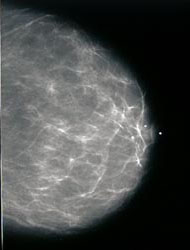

| Breast imaging (mammograms) utilize low dose radiation (x-rays) to image the breasts. Our equipment and mammography

programs are MQSA accredited by the FDA and ACR.

Breast biopsies, utilizing either ultrasound or digital x-ray images on a dedicated system are also offered as part of the Comprehensive Breast Center. Here patients have access to a multidisciplinary team for consultations, stereotactic biopsy, education, all in a convenient one-stop-shop setting. This is located in the Ruppert Health Center at the University Medical Center on the main campus of the Medical University of Ohio. |